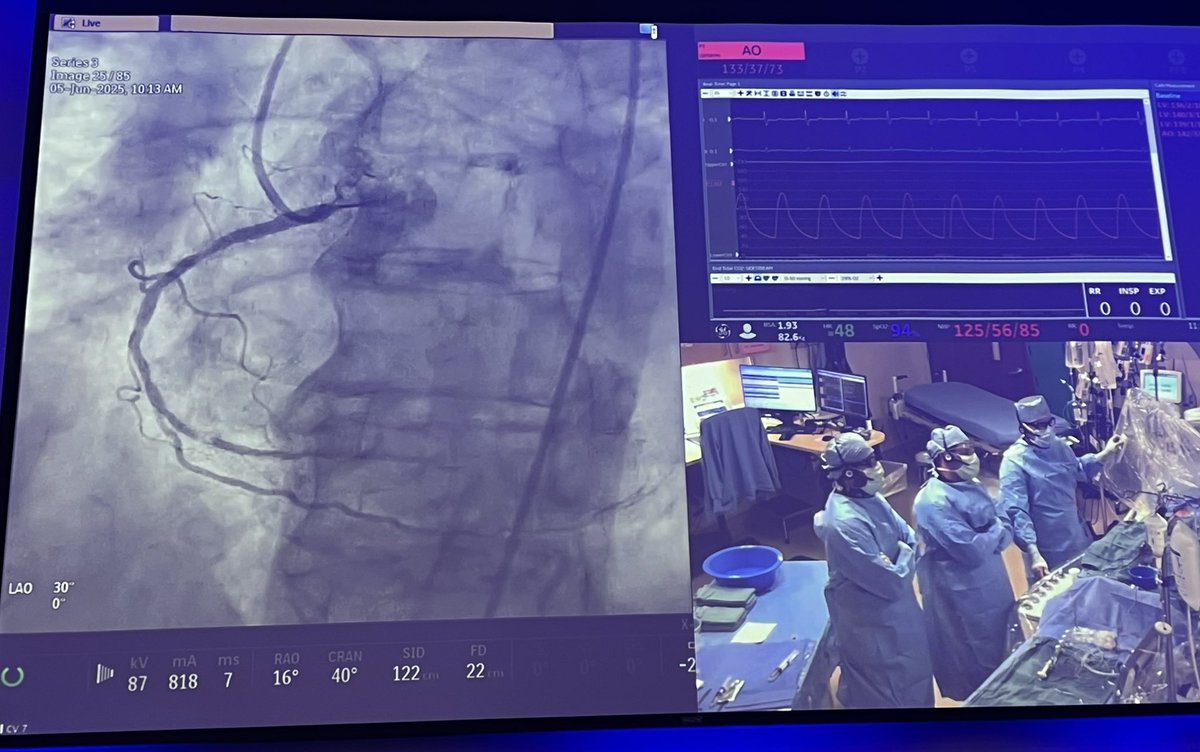

Live #PCI case from The Physiology Course Real-time learning in action — bridging theory and practice to show how coronary physiology is applied in the cath lab. Emmanouil Brilakis Yader Sandoval #PhysiologyFirst Minneapolis Heart Institute Foundation

The secret to a great live case? A top-notch panel and engaged commenters. Using physiology to guide decision-making in #PCI — moving toward more precise interventions. Bernard De Bruyne #PhysiologyFirst Yader Sandoval Emmanouil Brilakis Carlos Collet MD PhD William Fearon Morton J Kern R. Jay Widmer